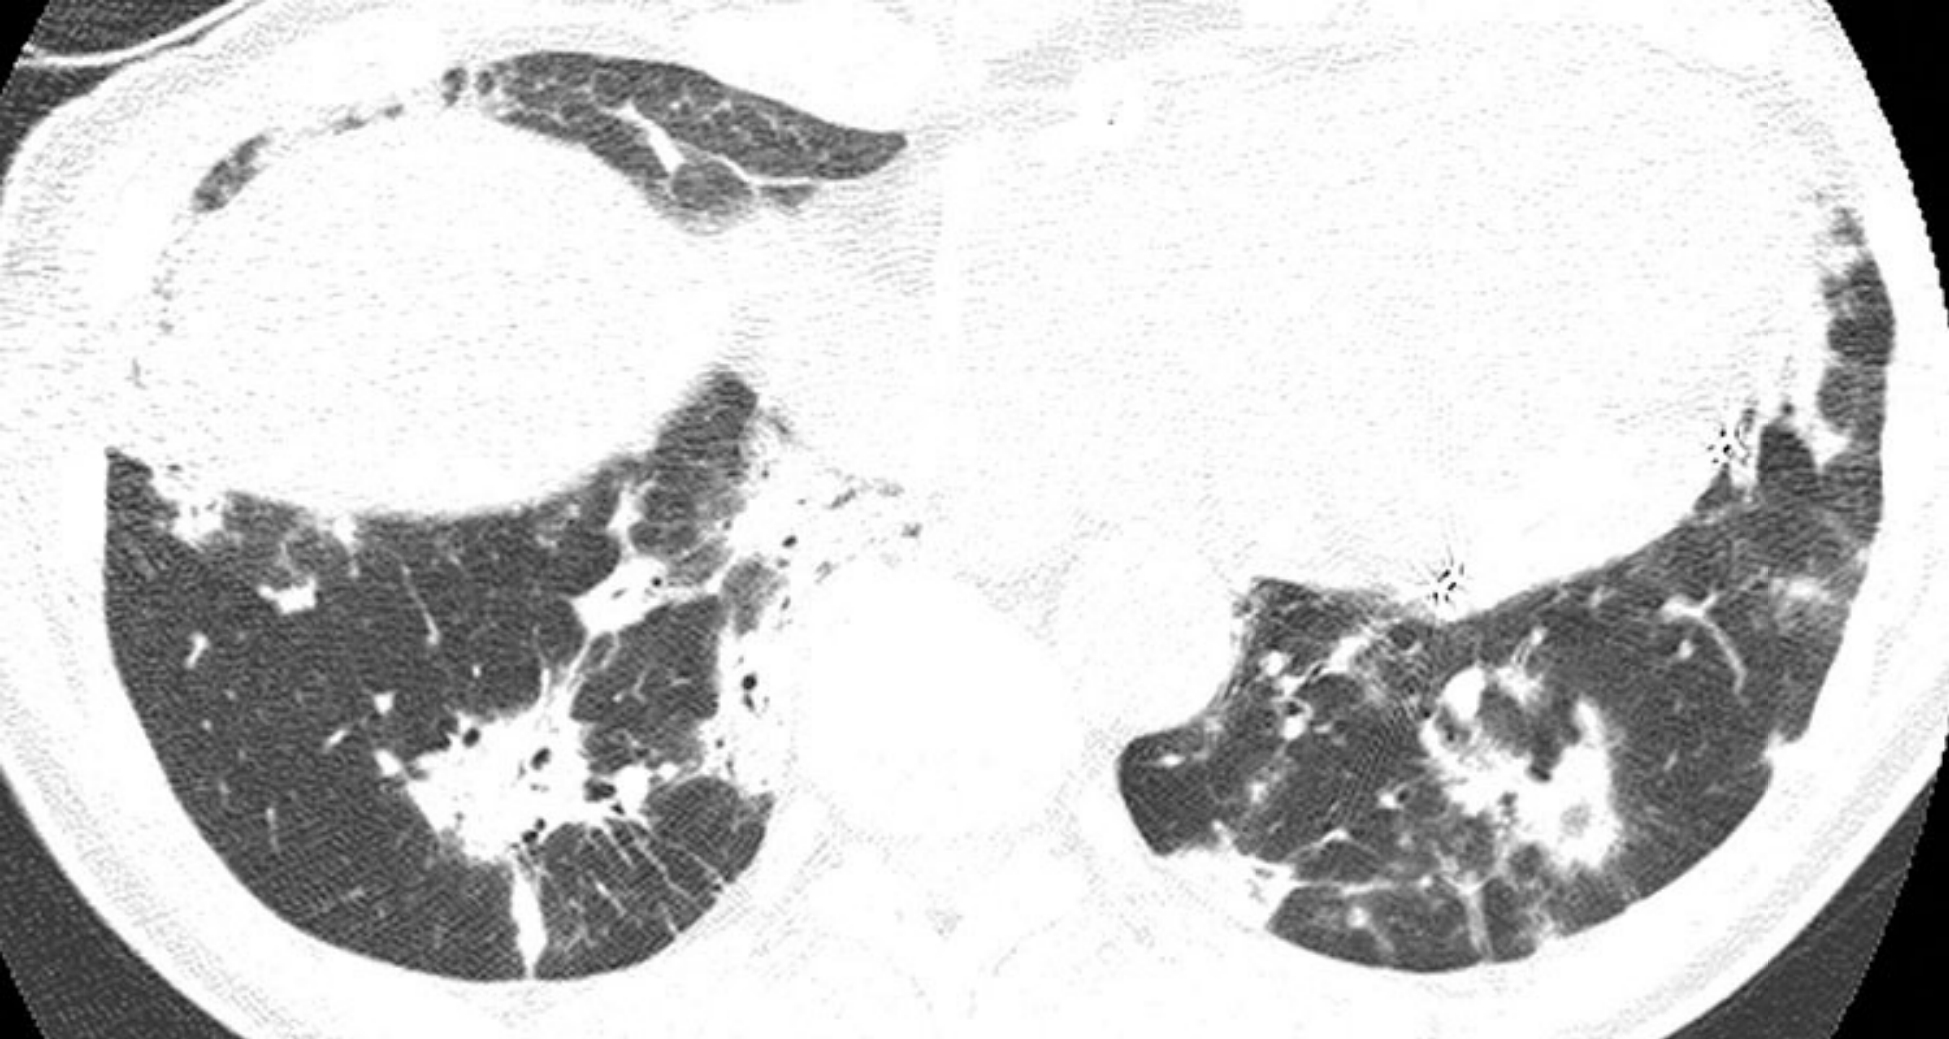

207a358047bcebd76d6336596b2ccc4d.png

间质性肺炎的病理表现。

A.在低倍镜下,普通型间质性肺炎有着明显的时间和空间异质性,表现为镜下可见胸膜下分布的蜂窝征(含气囊肿)而中央肺组织的纤维化程度较轻;

B.在高倍镜下,成纤维细胞灶位于纤维化组织和较少受累的肺组织的交界处(箭)。